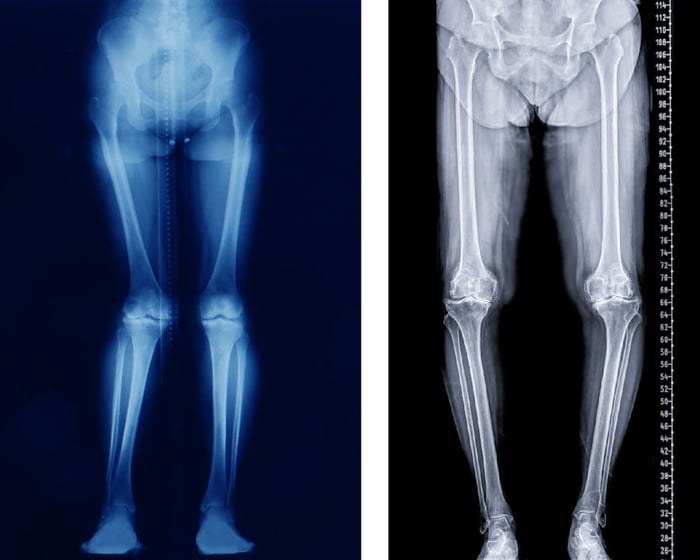

Diagnosi di valgismo e varismo: perché il carico è fondamentale

L’arto inferiore è il nostro pilastro strutturale: lavora sempre in carico, sostenendo il peso corporeo.

Per questo motivo, le valutazioni devono essere eseguite in posizione eretta: il carico modifica angoli e relazioni articolari, e certe deformità si manifestano solo quando il peso è realmente distribuito sugli arti.

Storicamente, l’ortopedia ha utilizzato:

- Rx bacino in carico

- Rx ginocchia in carico

- Rx piedi e caviglia in carico

Queste radiografie hanno permesso di valutare l’allineamento globale e pianificare interventi di riallineamento, come le osteotomie correttive.

A questo si aggiungeva TeleRx arti inferiori che offriva una prospettiva dell'intero arti e permetteva di studiare eventuali dismetrie.

Ginocchio varo e valgo

Nel caso del ginocchio si registrano due condizioni:

- Ginocchio varo: con un asse meccanico che devia verso l’interno, creando gambe “a O”. Il carico aumenta sul compartimento mediale: un ginocchio varo si rovina al suo interno!

- Ginocchio valgo: con un asse meccanico che devia verso l’esterno, ovvero le gambe “a X”, con sovraccarico laterale.